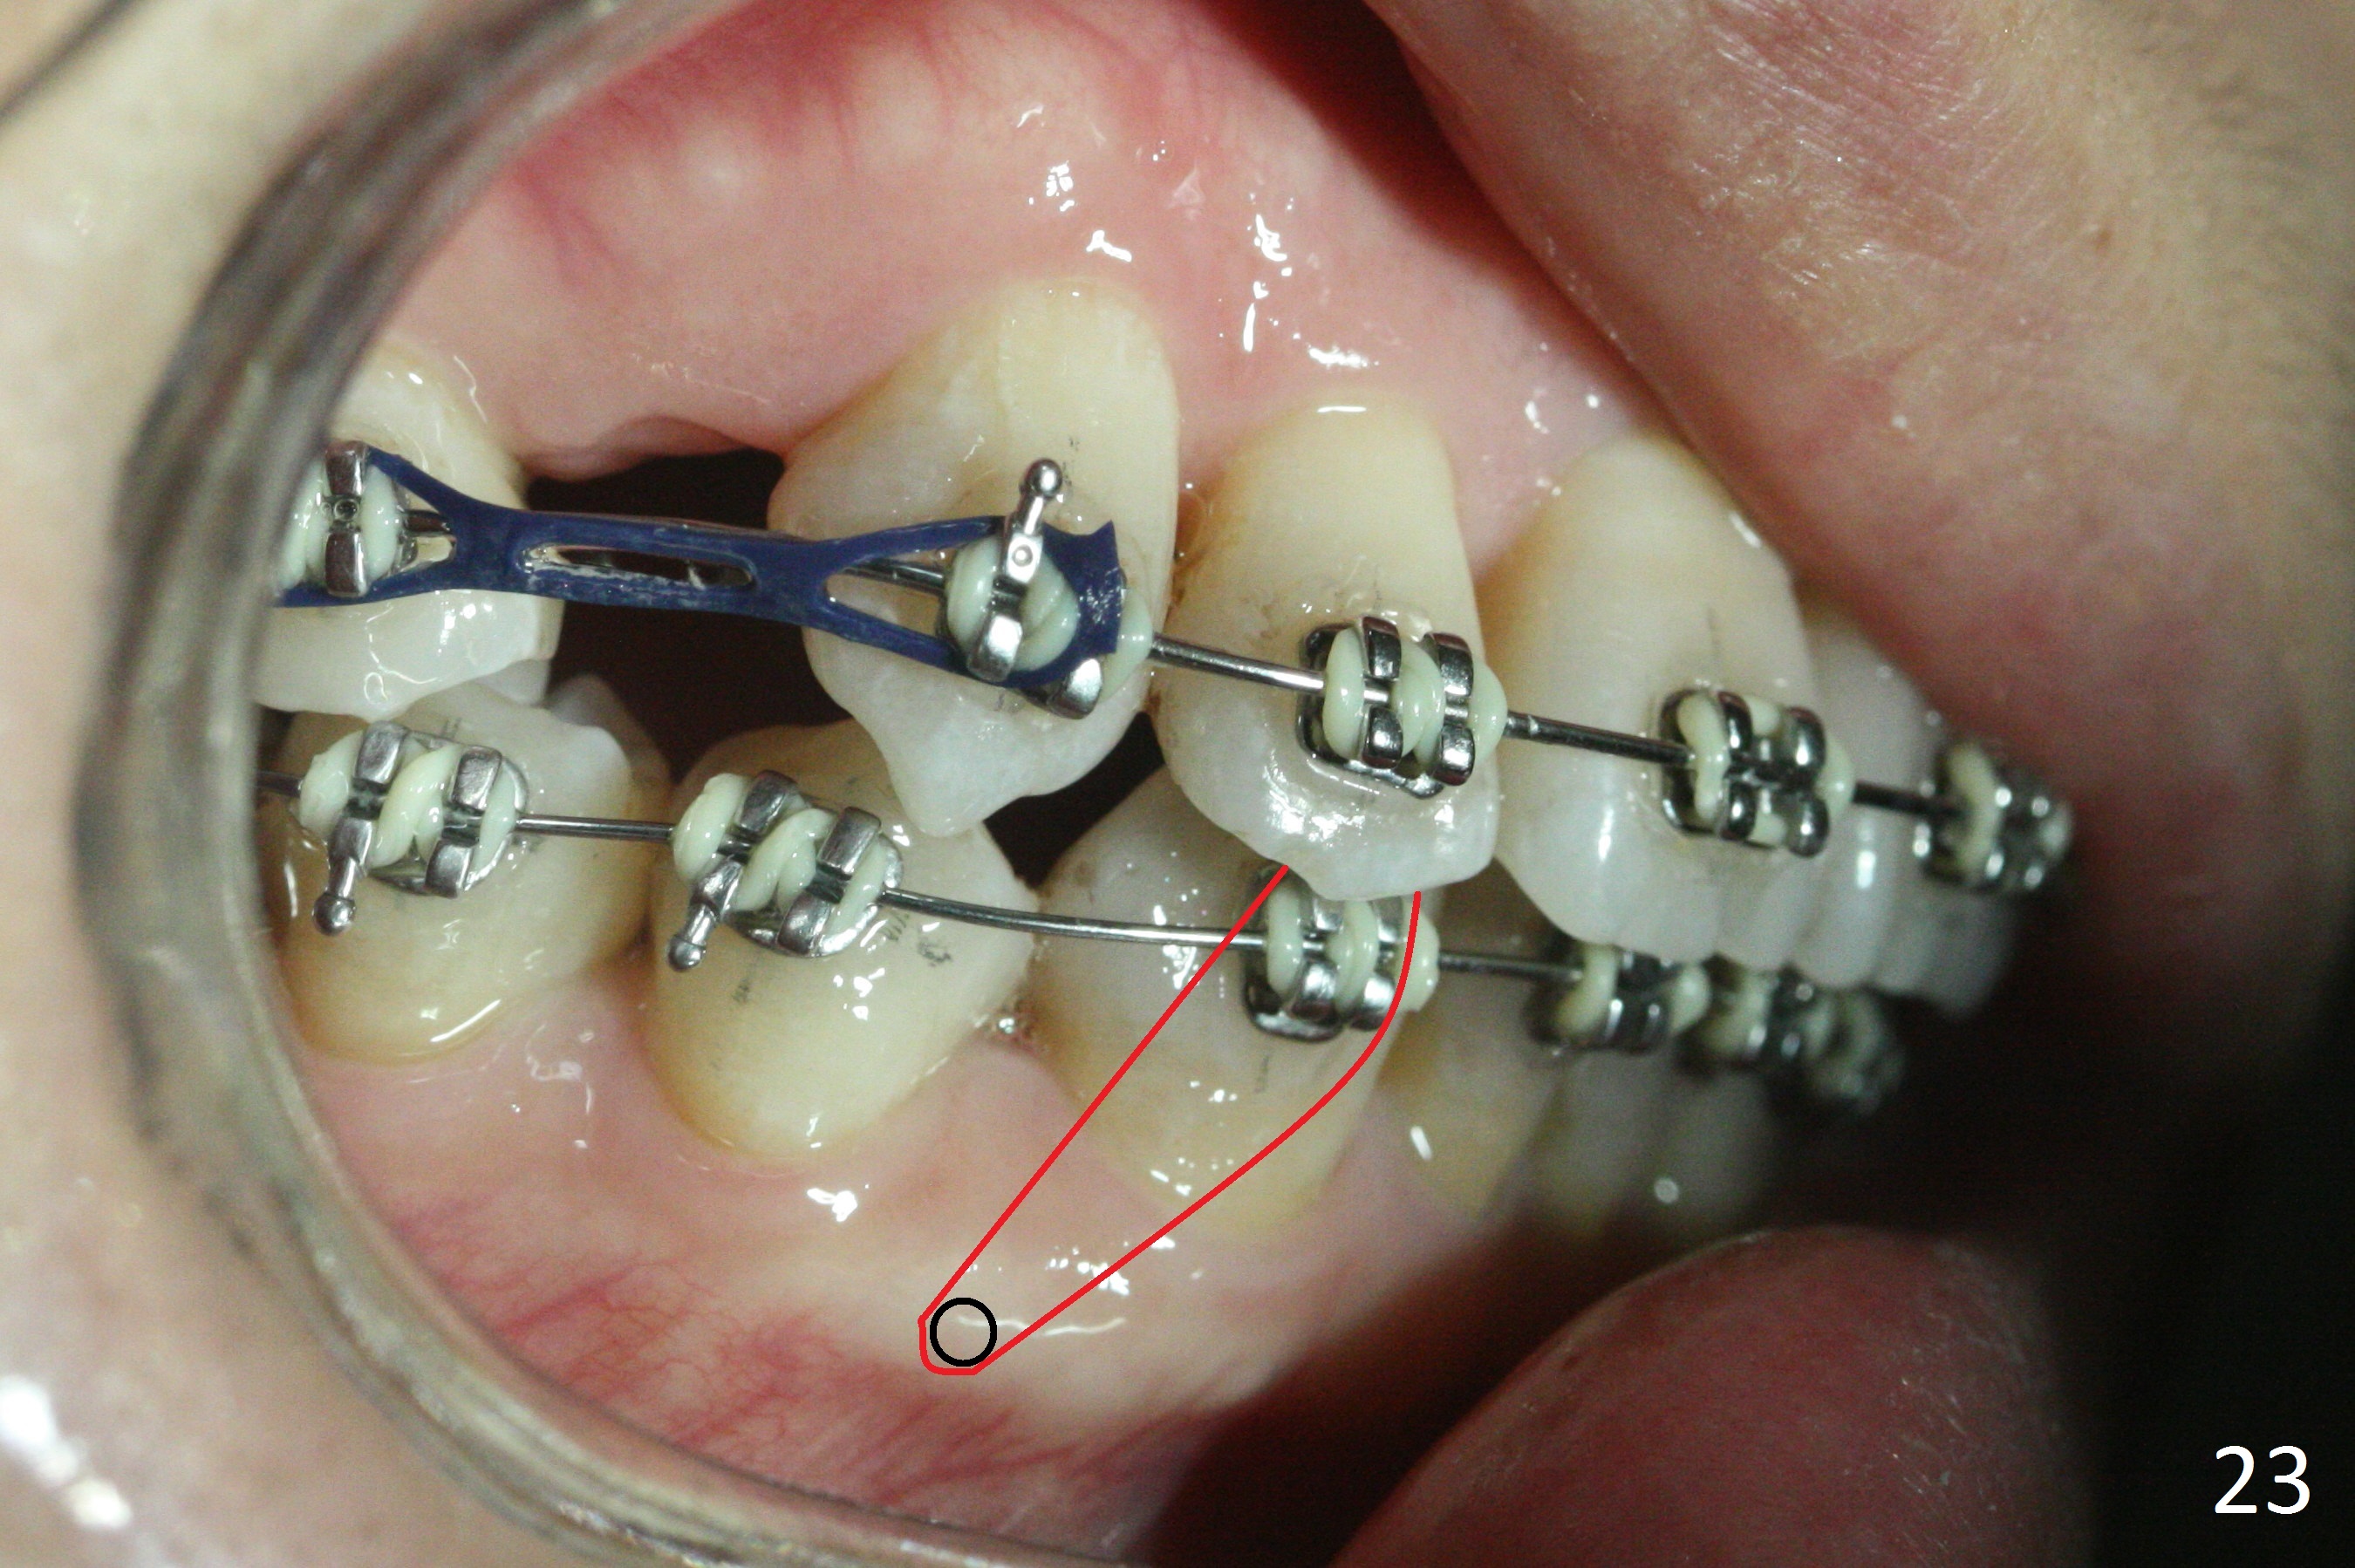

The rotation of the upper canines is not corrected much in the next 3.5 months (Fig.21, as compared to Fig.18). Distalization of the upper right canine is implemented by power chain, but this is not sufficient because of the anterior deep bite. Note the tension of 18 niti wire between LR 3 and 4 (^). Mini implants are going to be placed mesial or distal to L3s (Fig.22,23 circles) to intrude the lower anterior teeth with elastic or power chain (Fig.23 red line, 24 black area). The upper anteriors will have space to be distalized (Fig.24 arrow). If necessary, proximal reduction will be accomplished at LR3 (extra wide, Fig.25 black outline) for further overjet correction (arrows).